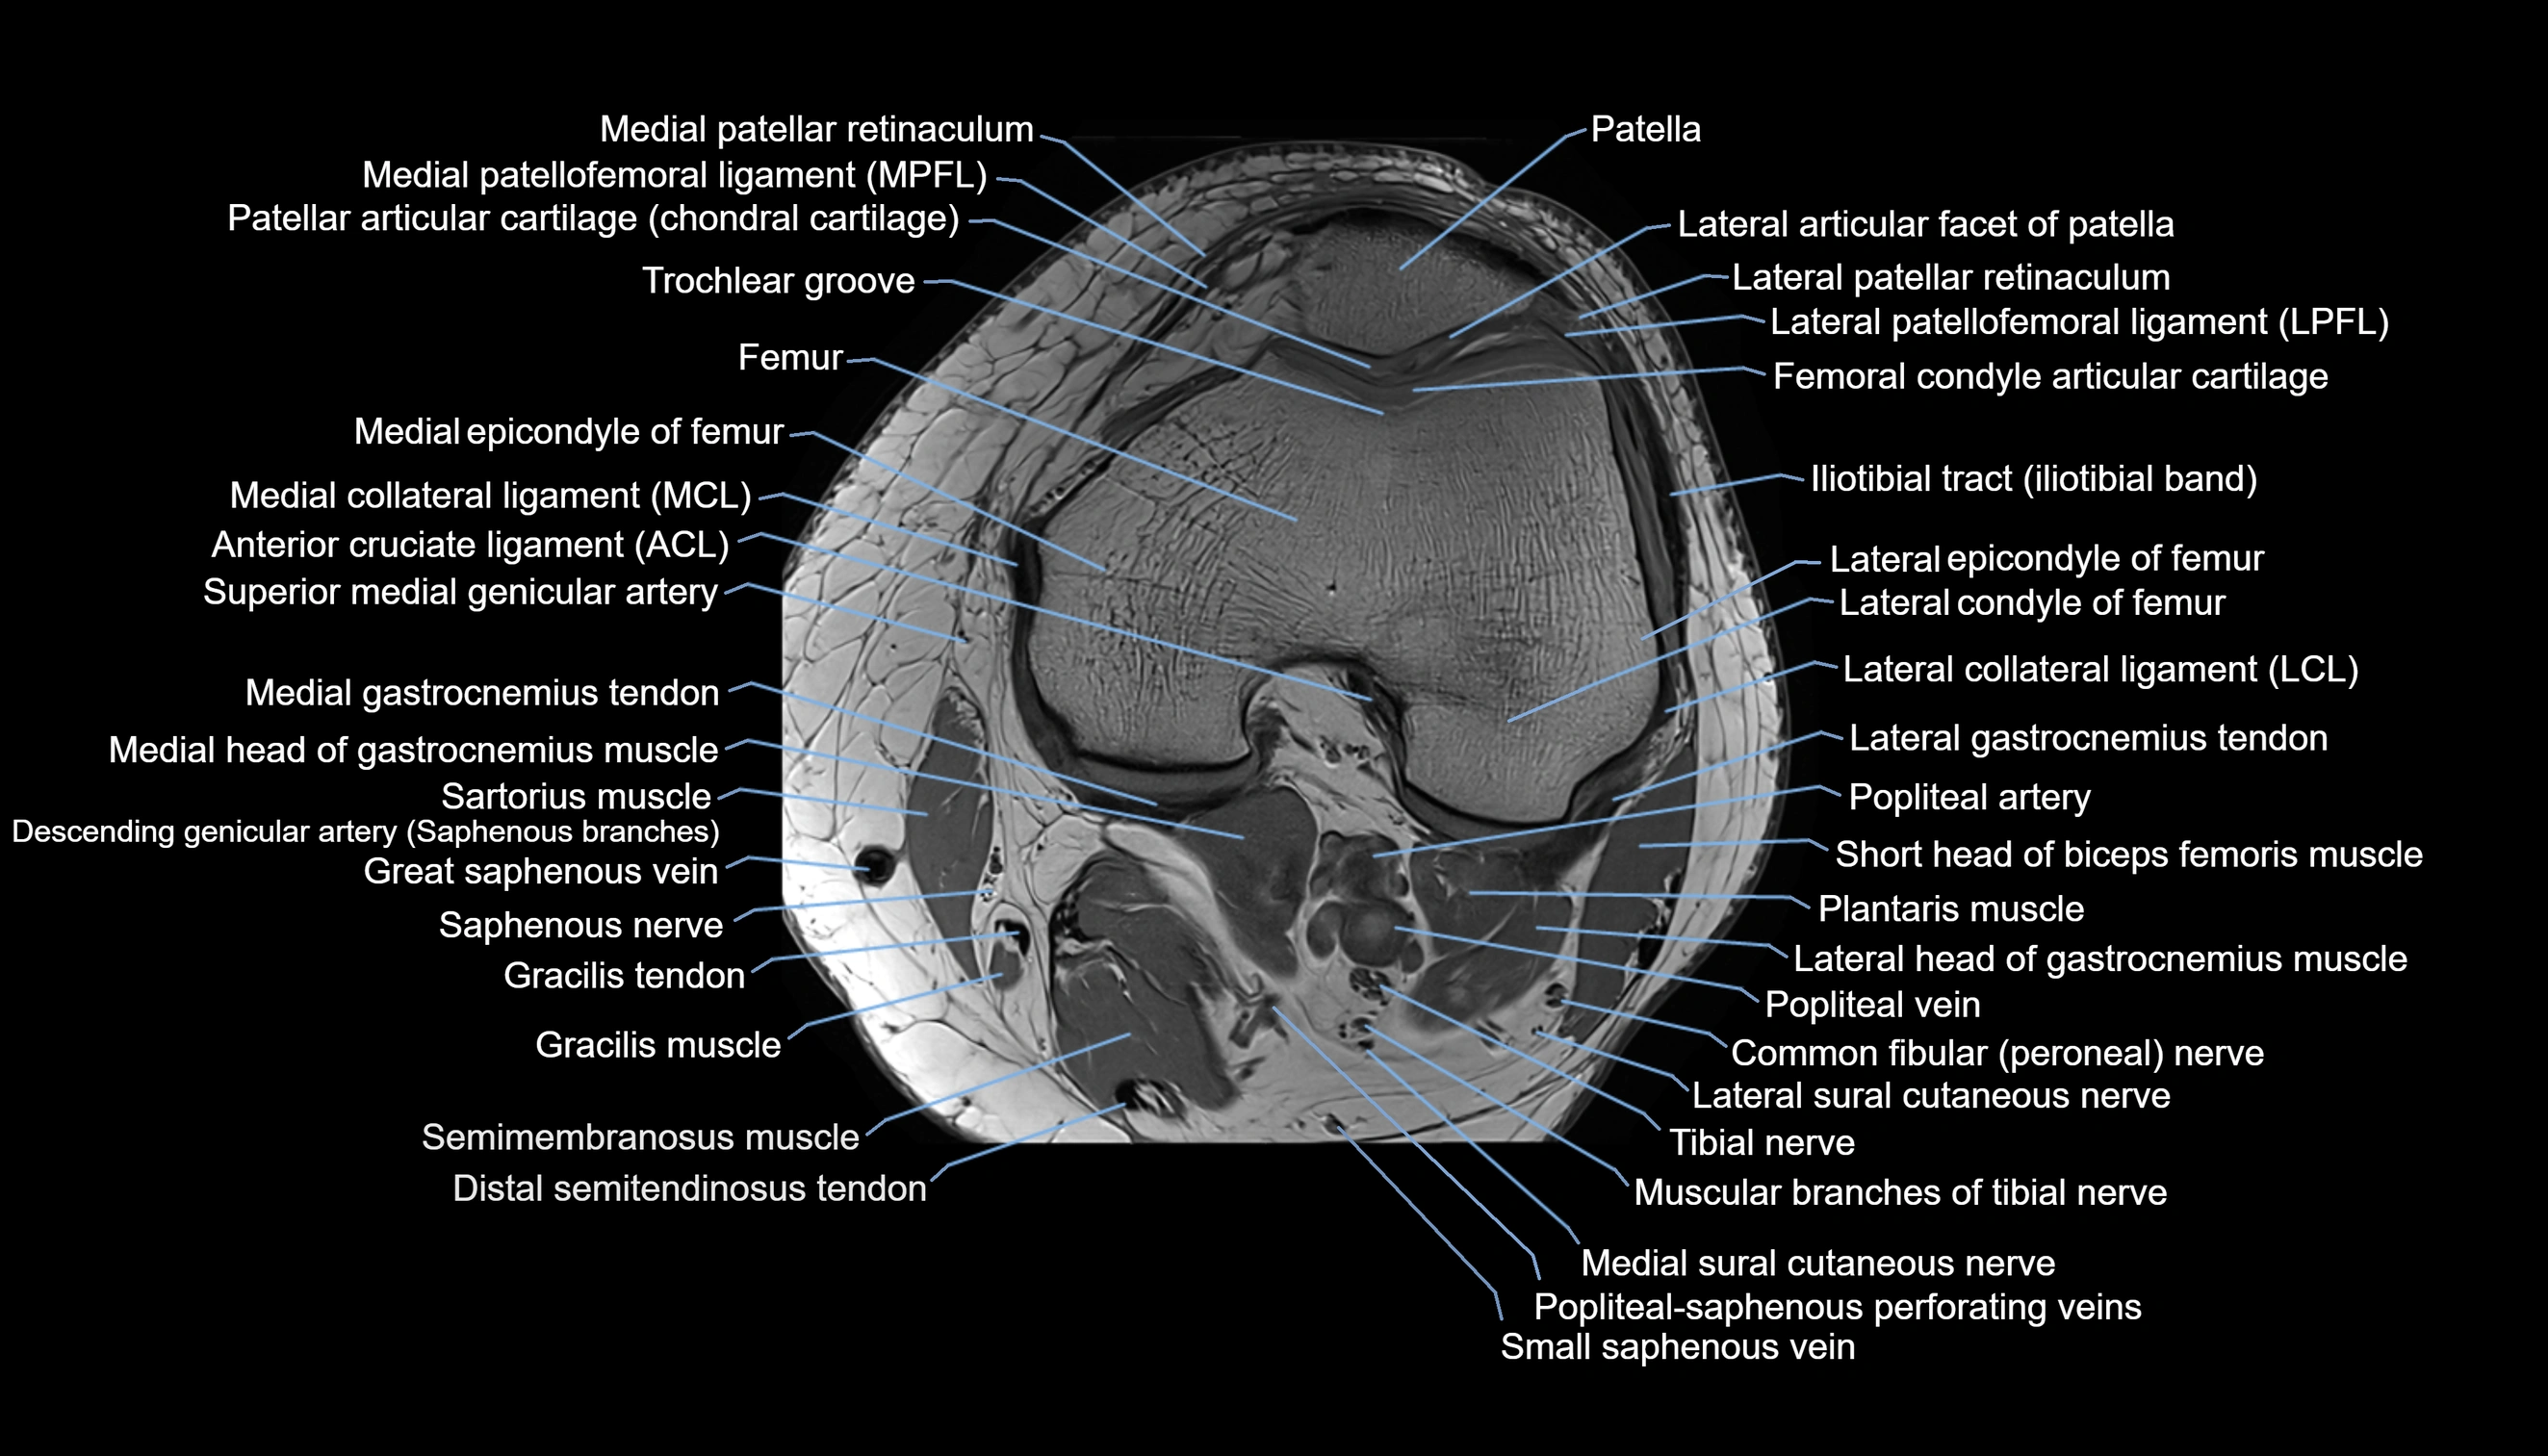

- Anterior cruciate ligament

- Lateral collateral ligament

- Medial collateral ligament

- Medial patellofemoral ligament

- Lateral patellofemoral ligament

- Femoral condyle articular cartilage

- Trochlear groove

- Popliteal artery

- Popliteal vein

- Tibial nerve

- Lateral sural cutaneous nerve

- Medial sural cutaneous nerve

- Small saphenous vein

- great saphenous vein